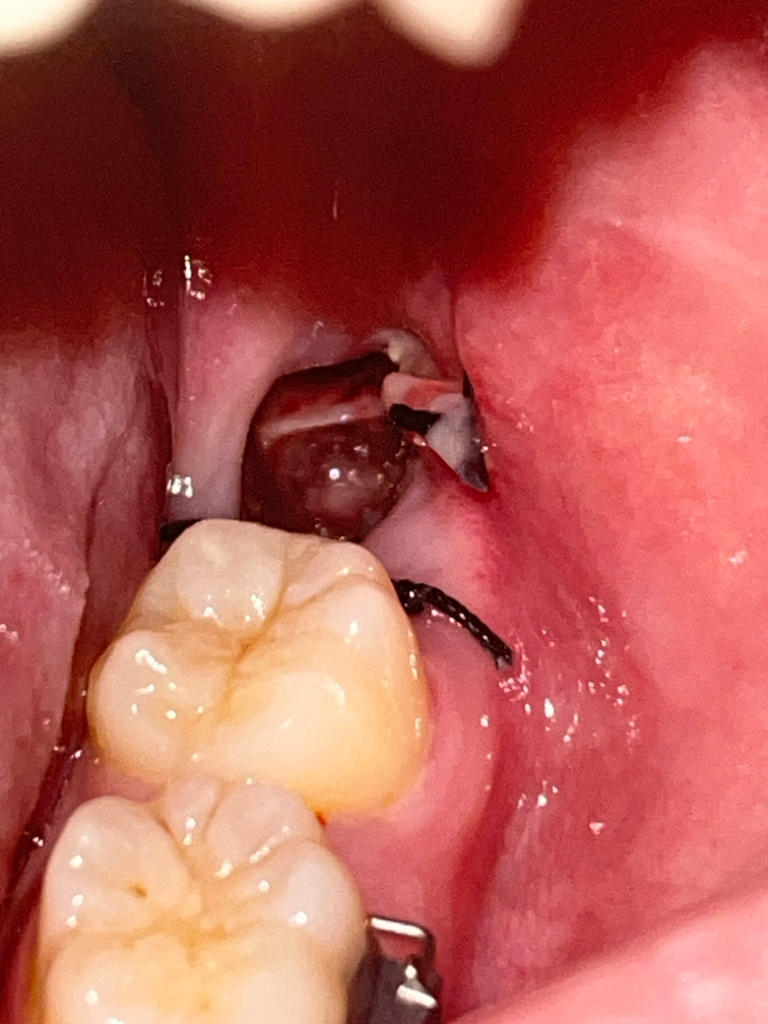

무서워요 드라이소켓인가요???

사랑니 발치 3일차인데 어느순간 저렇게 치조골이 보여요 ㅠㅠㅠ 통증은 잘 모르겠는데 욱신거려요 교정발치할때 드라이소켓 한번 걸렸었어요ㅠㅠ

드라이소켓은 감염의 일종입니다. 냄새가 많이 나고 통증이 극심합니다. 드라이 소켓은 아니고 발치한지 얼마 안되서 욱신거리신걸꺼에요.

드라이 소켓이 있는 경우 해당 부위에 냄새가 나고 과도한 통증이 있습니다. 통증이 없고 냄새가 나지 않는다면 드라이 소켓이 아닐 가능성이 높습니다. 발치한 부위는 자극하지 않는 것이 치유에 도움이 됩니다